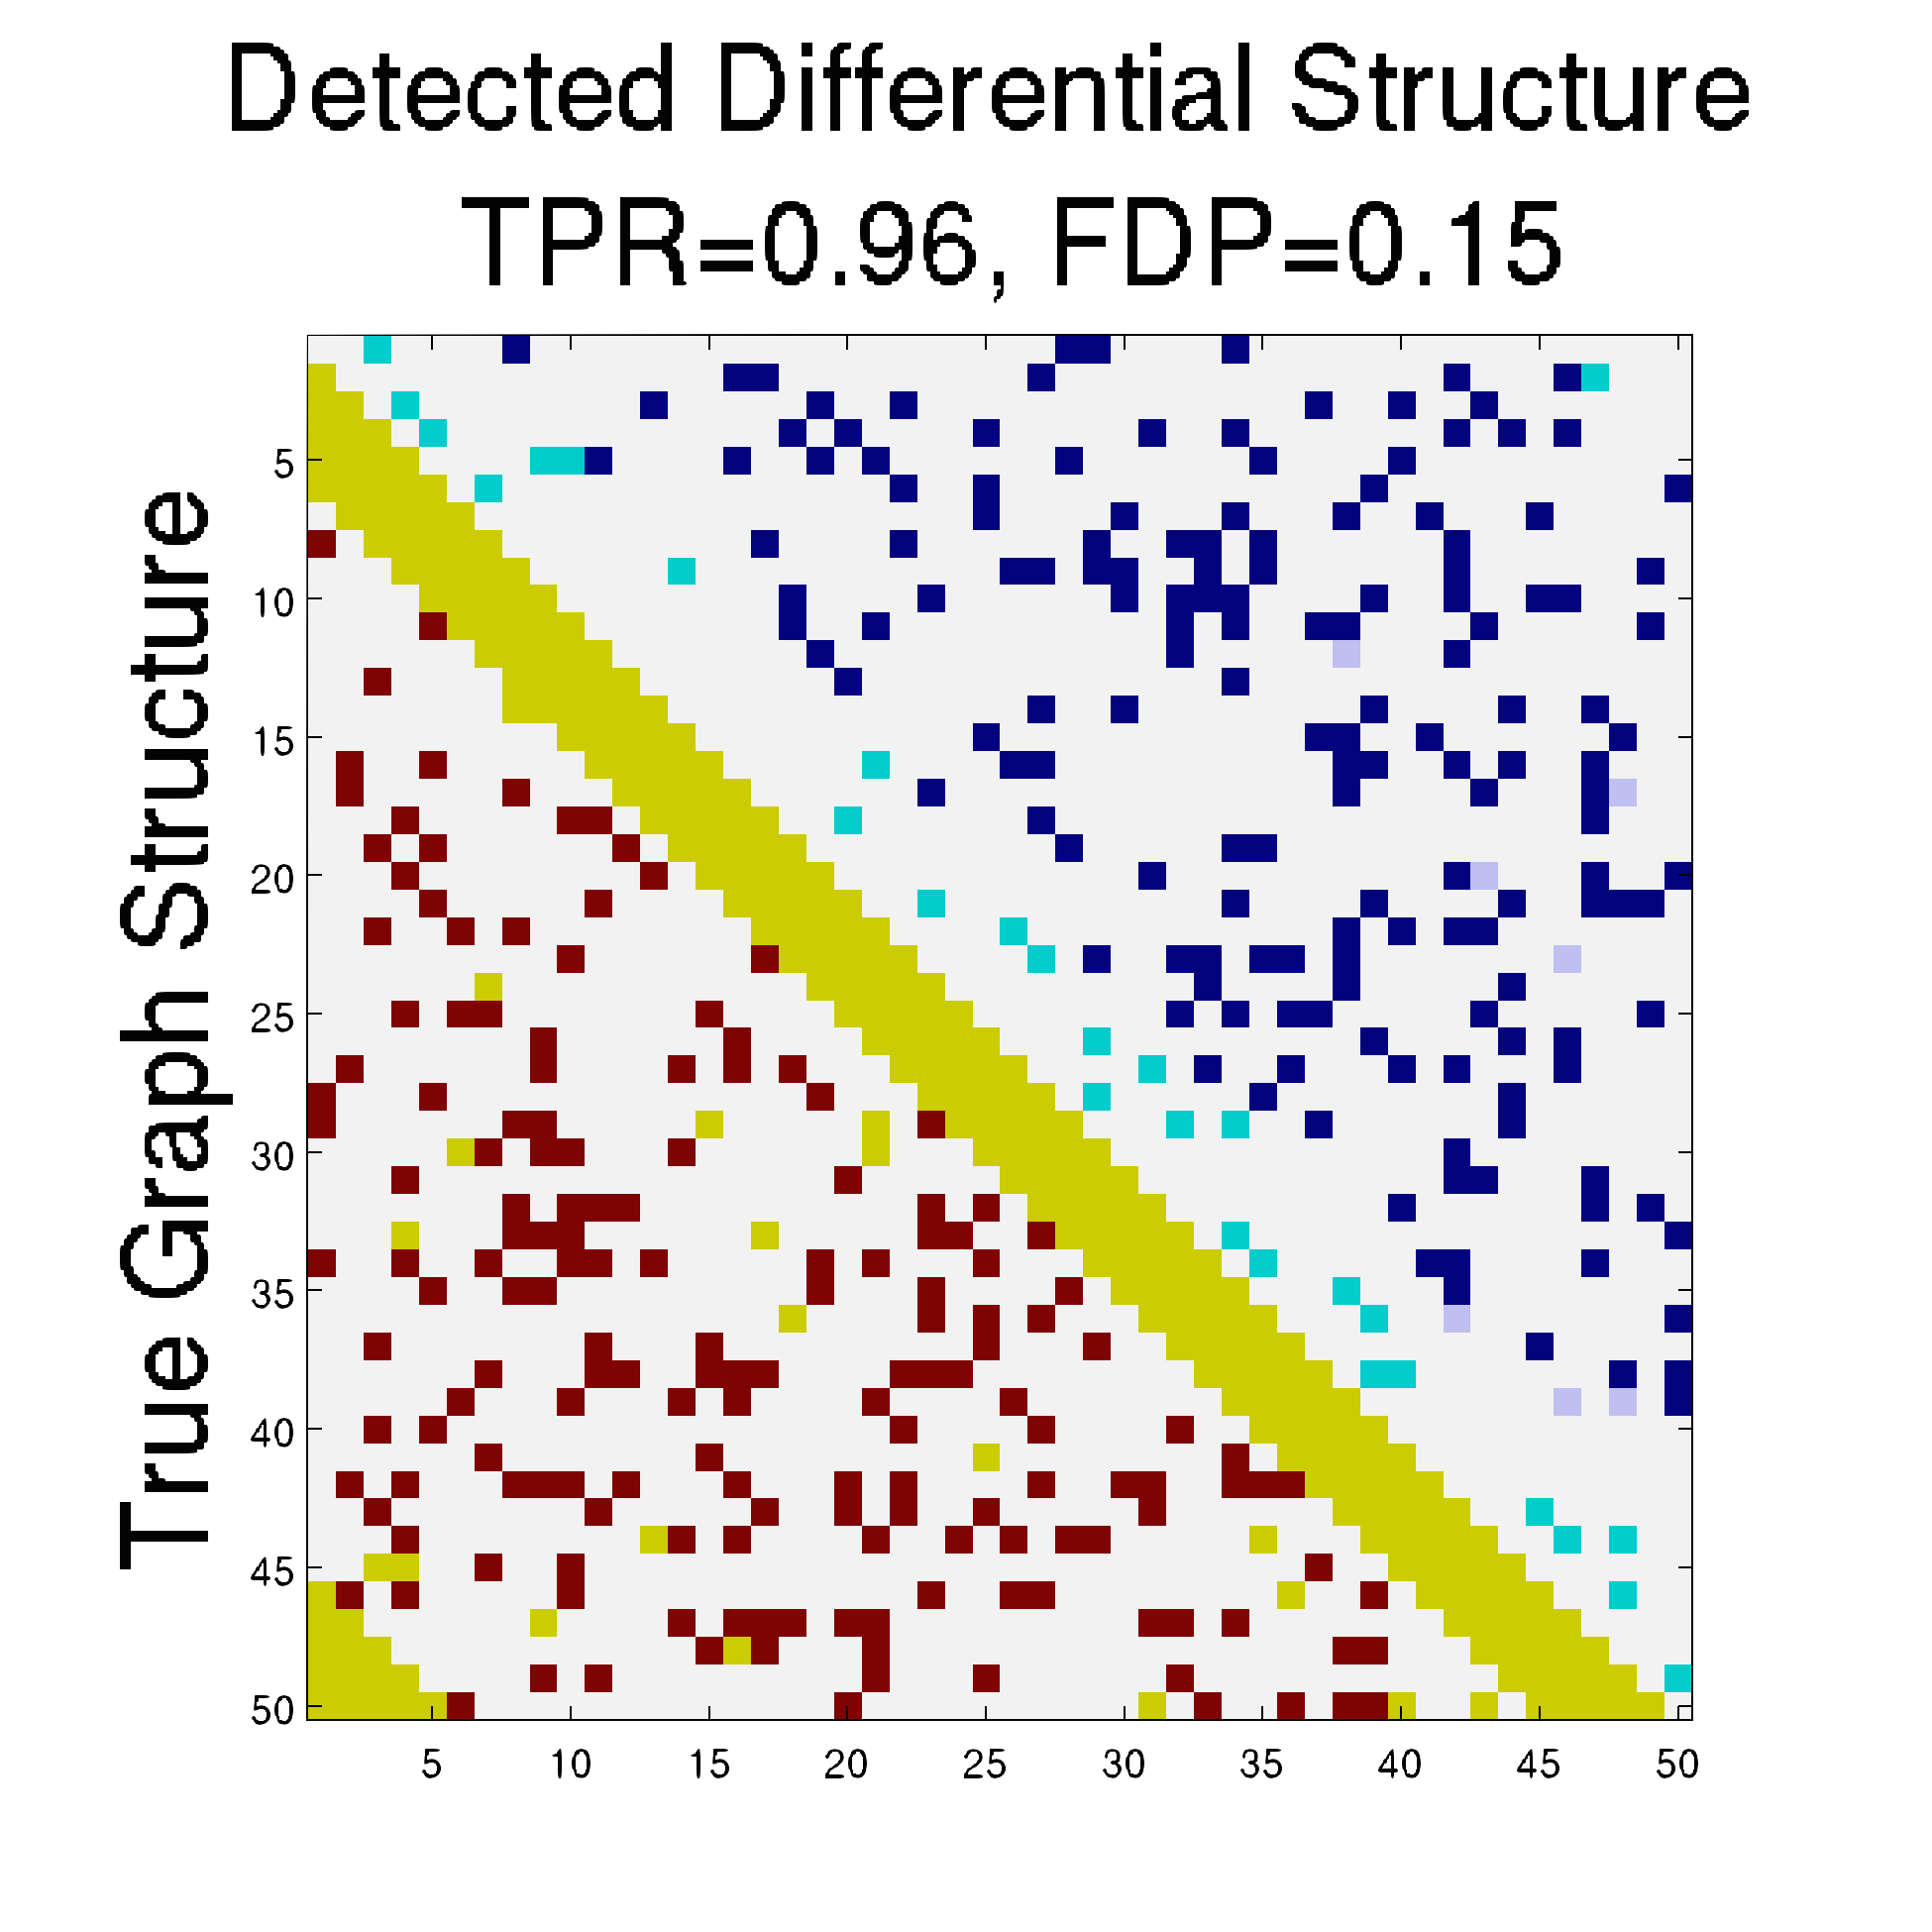

To understand the performance of this standard method, we present a small preview of our simulation study discussed later in Section 4. Briefly, we assume that each subject graph in group follows a small-world structure on nodes; in group , there are in addition 150 differential edges, meaning that and for all differential edges, . We generate data according to this model with time points and subjects in each group. Figure 1 illustrates the results of this standard approach as well as our new procedure, , which we will introduce later in Section 3. Part (a) gives ROC curves for the number of false positives verses true positives as each sequential test is rejected; parts (b) and (c) give the adjacency confusion matrix illustrating where the true and false positive as well as false negative edges are detected in the graph structure.

Our motivating simulation shows that the standard approach performs terribly in terms of both error control and statistical power. While the magnitude of the poor performance of this approach may seem astonishing, the poor performance should come as no surprise: The inferential procedure (e.g. test statistics) of the standard approach assume a one-level model that would be appropriate when the subject graphs are fixed and known or directly observed quantities. When these subject networks are unobserved, however, and must be estimated from finite data, these one-level test statistics are incorrect for our two-level problem. Specifically for two-level problems, the variance of parameters estimated by incorrectly assuming a one-level models is underestimated. For our problem, the extra source of variability arises from the graph selection procedure; we discuss challenges associated with this subsequently in Section 2.2. Incorrect variance estimates, however, are not the only problem with the standard approach: A more subtle problem arises from the fact that the proclivities of graph selection procedures for the Gaussian graphical model lead to biased estimates of the edge proportions, . As discussed in Section 2.3 and seen in Fig 1, graph selection false positives and false negatives do not occur at random throughout the network structure, leading to biased group level estimates.

Hence, the first term represents variability across subjects in group and the second term represents the variability associated with the selection procedure within subject , a quantity that we assume to be constant across subjects in each group . Consider now what happens if our true model follows this two-level Beta-Binomial model, but as with the standard approach, we use a one-level Binomial model and associated two-sample test statistic. The variance is thus underestimated and the test statistic is overoptimistic. Then, when inference is conducted for the population mean , using the incorrect Binomial model leads to inflated Type I error rates; this behavior has been well-documented (Weil, 1970; Liang and Hanfelt, 1994). Hence, failure to use the correct two-level model which accounts for the two levels of network variability partially explains the high error rates of the standard procedure observed in Figure 1.

In Figure 4 and Table 1, we present our main simulation results comparing to the two variations of our method and the standard approach for three network structures and Case I and II type differential edges. First for Figure 4, we report results in terms of operating characteristics averaged across 50 replicates with the number of true positives (y-axis) plotted against the number of false positives (x-axis) for each test statistic, rejected sequentially from largest to smallest in absolute magnitude. Overall, all of our methods and particularly yield substantial improvements over the standard approach in all scenarios.

Notice that both and =(RS,RP) share similar orderings of test statistics, and consequently similar ROC curves. Overall, methods that include random penalization yield major improvements in statistical power over those that do not. This indicates that the second popPSI challenge outlined in Section 2.3 is a significant contributor to the poor performance of the standard method. Recall our discussion of how graph selection errors at the subject stage occur non-randomly and hence bias our group-level estimates of . Our results empirically demonstrate that random penalization dramatically improves these biases, leading to less bias in our test statistics and hence improvements in both Type I and Type II error rates. Furthermore, in Case II scenarios where selection errors are moderate, the performance gap between any method containing over reduces compared to Case I scenarios where selection errors are more severe. Thus, the benefits of random penalization are greater when selection errors are more abundant. Confusion adjacency matrices illustrating the location of inferential errors for our methods shown in the supplemental materials also indicate that random penalization improves graph selection in cases where there are larger correlations between differential edges and common edges. Similar results hold for our high-dimensional study presented in the supplemental material.

Table 1, which accompanies Figure 4, gives the empirical true positive and false discovery rates (FDR) averaged over 50 simulation replicates when the Benjamini-Yekutieli (Benjamini and Yekutieli, 2001) procedure controlling the FDR at 10% is used to determine the number of tests to reject. First, notice that the observed false discovery proportion (FDP) of our procedure is not 10% on average, indicating that our method does not fully control the FDR. This occurs because we specifically simulate difficult and realistic fMRI scenarios with graph structures that severely violate irrepresentable-type conditions. In situations (not shown) where irrepresentable-type conditions are met that ensure graph selection consistency, our procedure as well as the standard method correctly control the FDR. As discussed in Section 2.3, in situations where graph selection errors occur with high probability, it is likely impossible to provably control the FDR, consistent with our empirical results. Yet even though does not fully control the FDR, our error rates are dramatically improved over the standard approach and other variations of our procedure.

Also in Table 1, observe that (RS,RP), which had similarly ordered test statistics to , has dramatically worse Type I error rates that do not come close to controlling the FDR. While (RS,RE) also does not control the FDR, the error rates are much improved over (RS,RP). These results demonstrate that using two-level models with the correct random effects test statistics are crucial to Type I error control. Recall from Section 2.2, that using the one-level Binomial model leads to an under-estimation of the variance term which in turn inflates test statistics and leads to an increase in false positives. Note also that the estimated FDP of is still a major improvement over that of (RS,RE). This occurs as the problem of graph selection errors induces both Type I and Type II errors. Hence, these results demonstrate the necessity of all three of our ingredients. Finally, observe that our error rates in Case II scenarios are better than those for Case I scenarios, again indicating that differential edges that are highly correlated with non-edges and common edges pose particular challenges for our popPSI problem. These results are also corroborated in our high-dimensional study presented in the supplemental materials.